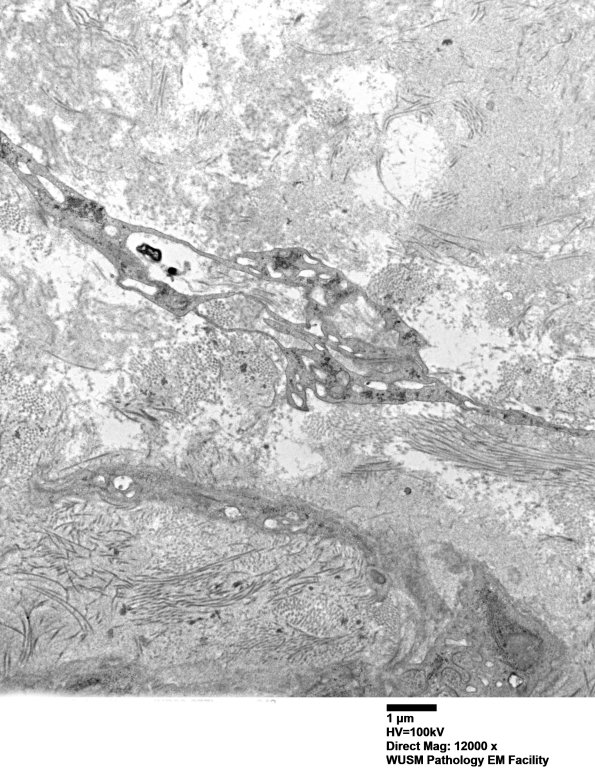

A fibroblast-like-cell shows cytoplasmic vacuolation. (electron micrograph)